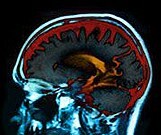

Study Examines Age, Sex, APOE ε4 Effects in Adults

Memory and adjusted hippocampal volume worse in men than women; no sex difference in amyloid PET